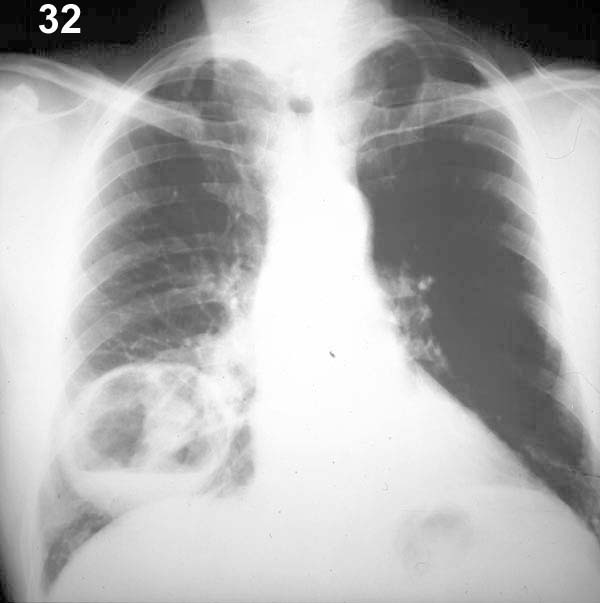

ESQUEMA 32 Comentario placa 32 El tamaño de esta cavidad es similar al de la anterior, pero la pared es más gruesa e irregular y la cavidad tiene un contenido hidroaereo. Además se ve una sombra redondeada de unos 3 cm. de diámetro que puede corresponder a restos necróticos en el interior del absceso, pero la radiografía frontal no permite descartar que no se trate de un nódulo o condensación situado detrás o delante de la cavidad. Esta imagen se puede generar por un proceso infeccioso abscedado o una neoplasia necrotizada. Analice la placa 33 |